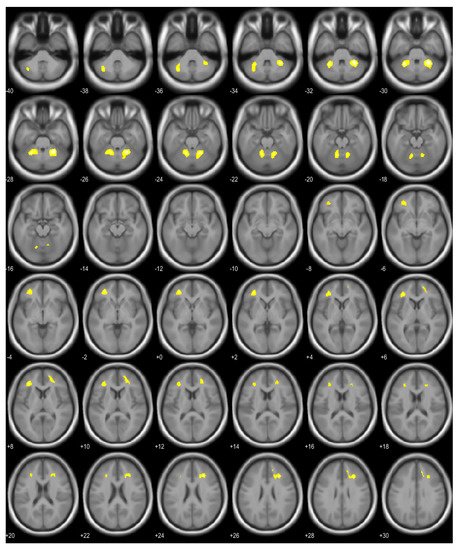

| Brain Area | Voxel | T | p (FWE Corrected) | Coordinates (x, y, z) |

|---|---|---|---|---|

| Right cerebellum, anterior lobe | 521 | 6.55 | <0.001 | 28, −48, −30 |

| Left cerebellum, anterior and posterior lobe | 522 | 6.19 | <0.001 | −30, −50, −30 |

| Right middle frontal gyrus, right cingulate gyrus, right anterior cingulate | 297 | 5.78 | <0.001 | 28, 30, 26 |

| Left middle frontal gyrus, sub-gyral area of left frontal lobe | 368 | 5.66 | <0.001 | −34, 38, 8 |

| Brain Area | Voxel | T | p (FWE Corrected for Cluster Level) | Coordinates (x, y, z) |

| Left cerebellum, anterior lobe | 458 | 4.87 | 0.009 | −24, −40, −30 |